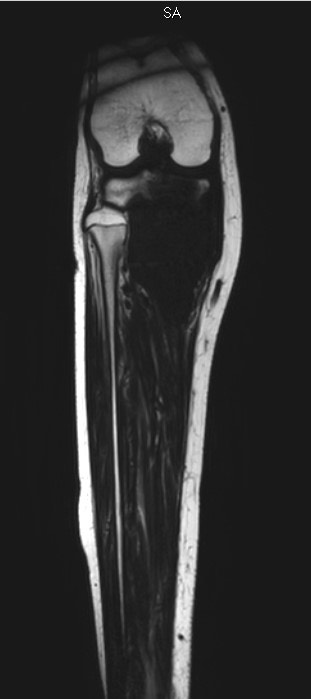

1332. Девочке 15 лет с жалобами на усилившиеся боли в области правого коленного сустава при нагрузке и в покое и появившейся отечностью правого коленного сустава, выполнена МРТ, заболеванием, соответствующим клинико-рентгенологической картине, считают остеосаркому _____ правой большеберцовой кости